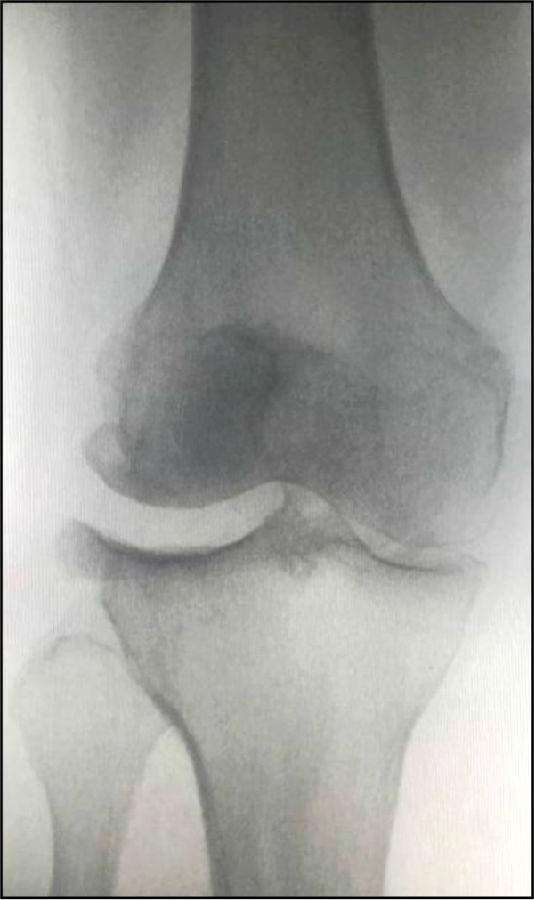

5. 外侧间室OA病理学特点

股骨髁磨损;胫骨平台磨损

LCOA的磨损在胫骨平台后侧,股骨髁磨损从屈曲45°开始,随着病情发展逐步向前、向后,主要以后侧为主。LCOA早期时在伸直位通常没有畸形,当临床发现有外翻畸形时,此时病情已经发展较重。

术前